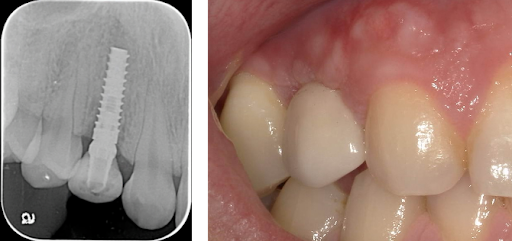

Gingival recession